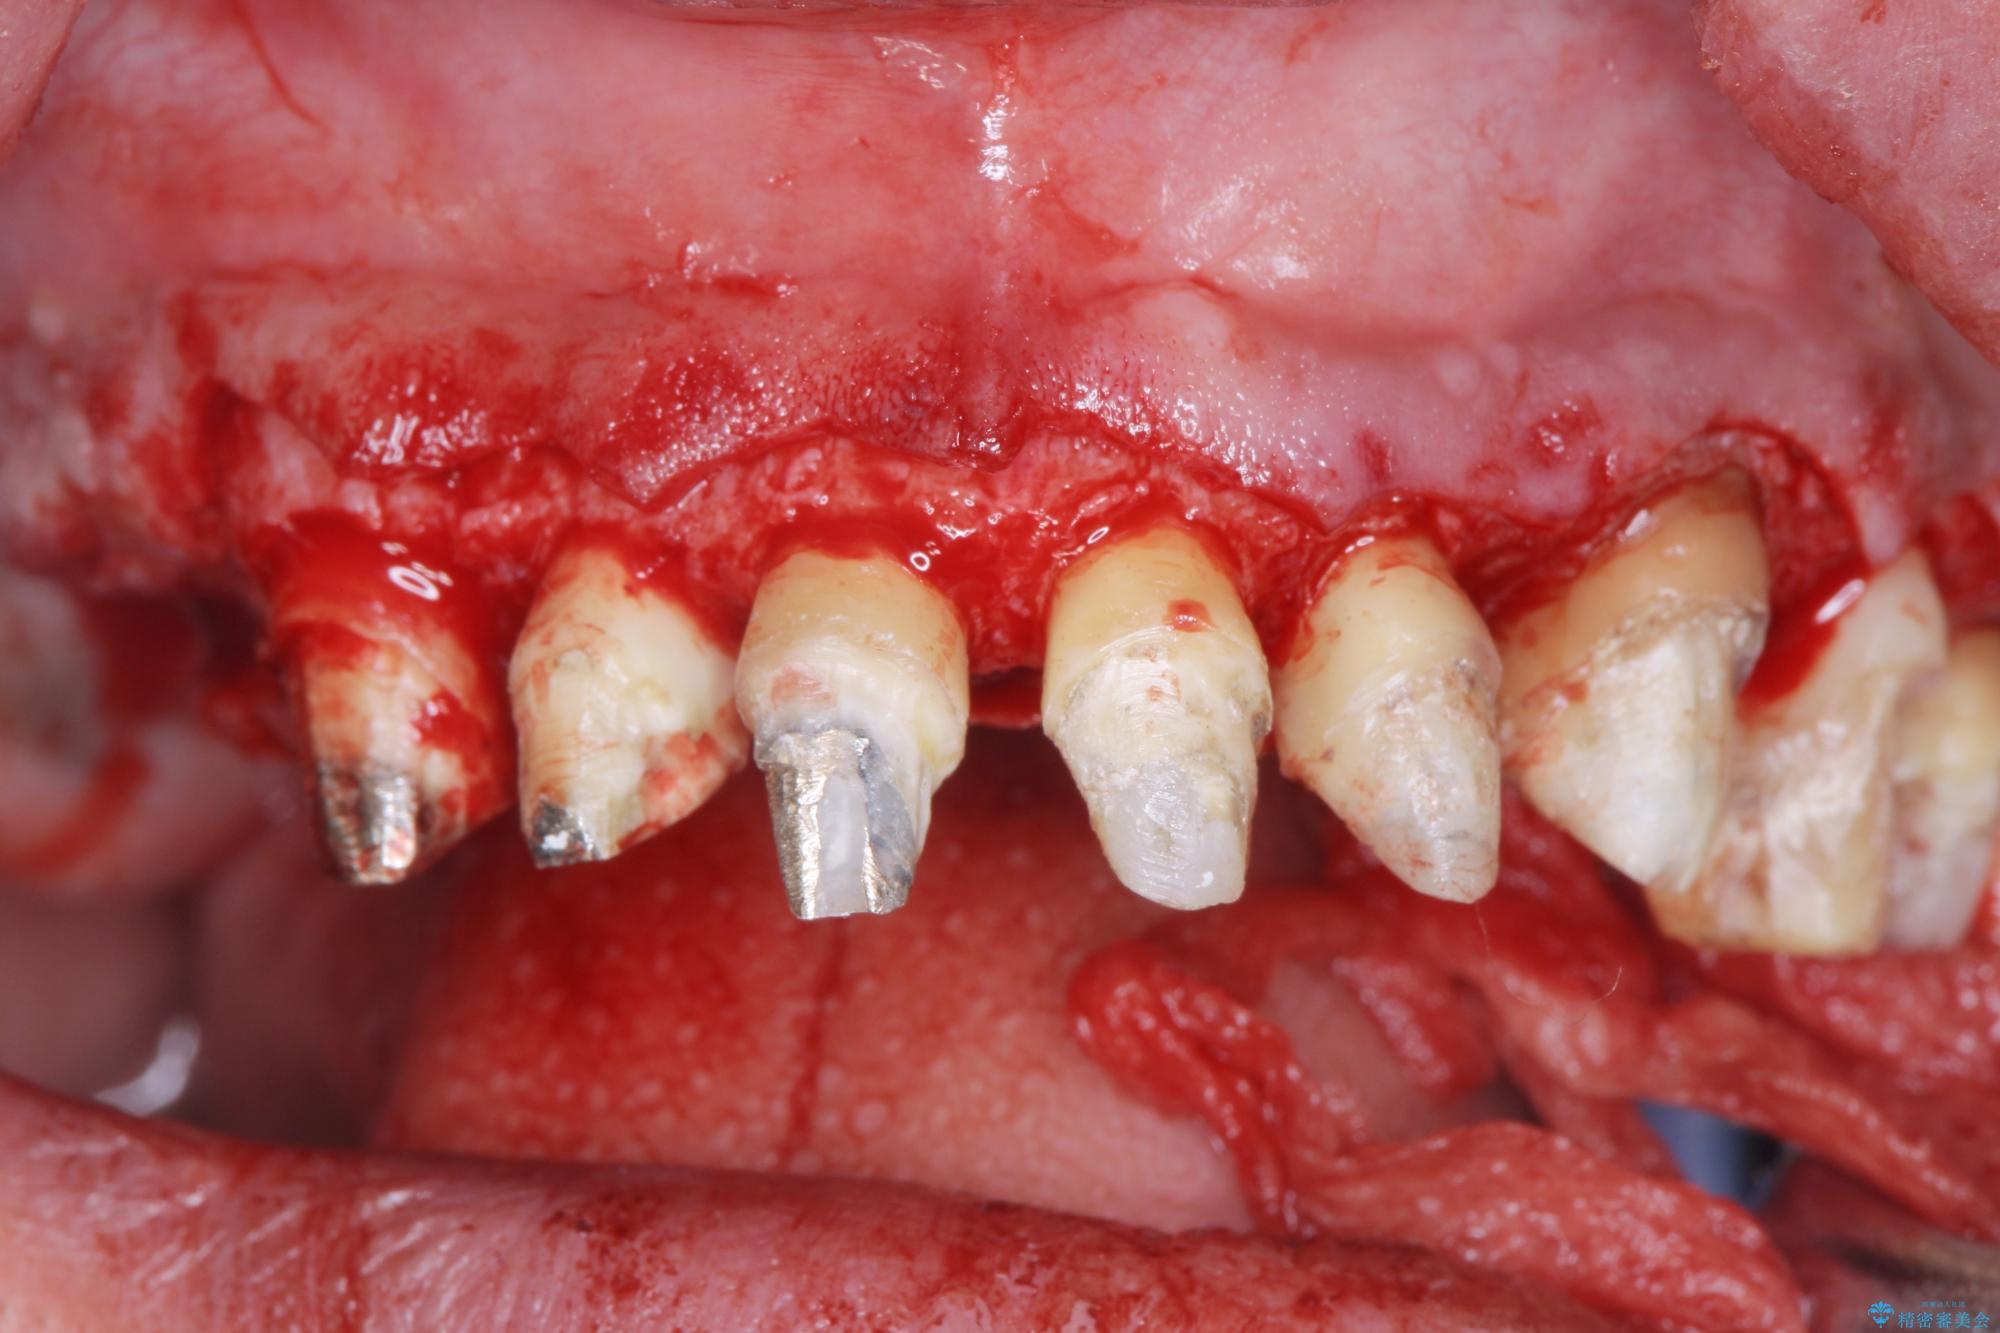

セラミッククラウンを除去し仮歯を装着し、歯周外科手術を行い歯ぐきの状態を改善したのち、適合の良いセラミッククラウンを再作製をする治療計画としました。

- 90.2万円(ジルコニアクラウン×6・仮歯×6 ・歯周外科手術)費用は治療当時の料金となります

- 外科手術のため、術後に出血、痛みや腫れ、違和感を伴います